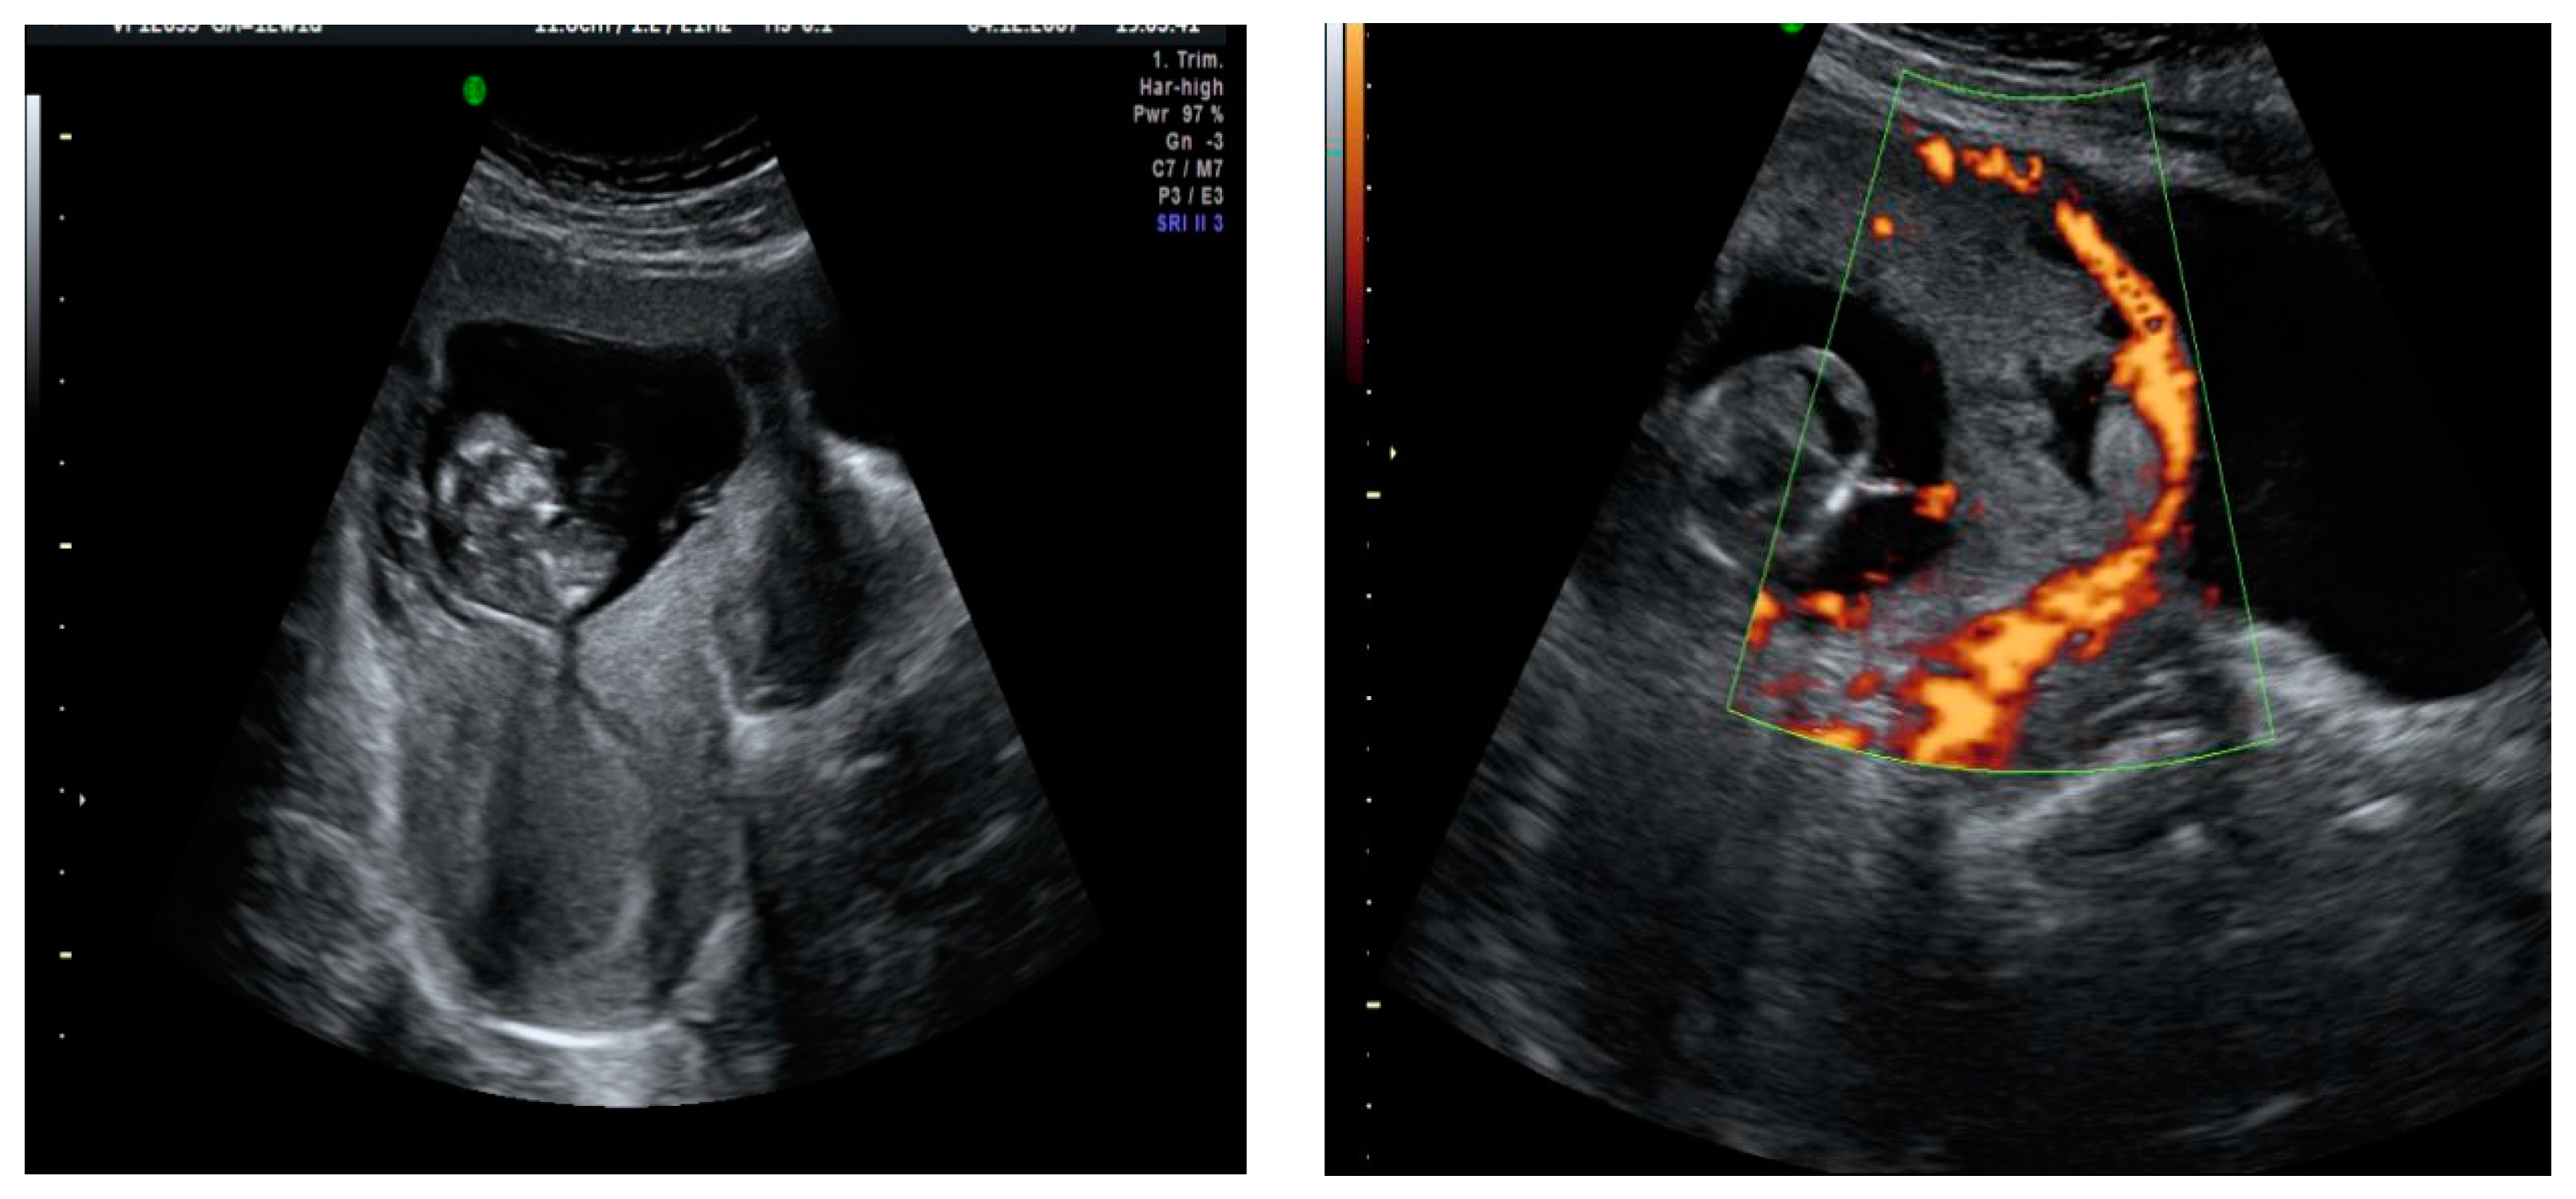

A transvaginal ultrasound was performed (Figure 2), revealing a retroflexed uterus with endomyometrium measuring 6 mm, a gestational sac of 15 mm, and an embryo of 3.6 mm with positive cardiac activity located on the cesarean scar. The bladder was not invaded, and there was normal adnexal and a small amount of free fluid in the pouch of Douglas. The patient’s serum determination of betahCG was 14,508 UI/L.

Figure 2. A sagittal transvaginal image showing a gestational sac implanted in the scar area of the previous cesarean with a 3.6 mm embryo.